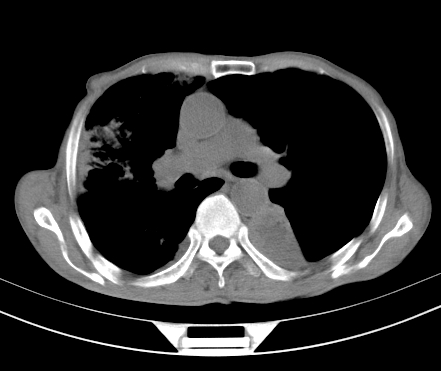

以下是引用gaoshengjiang在2008-5-30 19:53:00的发言:[br]右上叶可见大片实变影,其内可见充气支气管影及囊状影,右上叶尖端支气管走形区可见结节样影,左侧胸腔内可见胸腔胃影。纵隔淋巴结肿大。[br]考虑:1.右上肺阻塞性肺炎伴肺脓肿形成。支持转移所致。[br] 2.左侧胸腔胃。